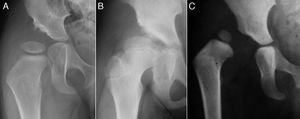

El término displasia del desarrollo de la cadera (DDC) incluye un amplio espectro de alteraciones del acetábulo y del fémur proximal, incluyendo la displasia aislada, la subluxación o la luxación de la cabeza femoral1–4 (fig. 1). En la displasia existe un desarrollo inadecuado del acetábulo, de la cabeza femoral o de ambos, aunque hay una relación concéntrica entre ambas superficies articulares. Sin embargo, en la cadera subluxada, aunque hay contacto entre las dos superficies articulares, la cabeza femoral no está centrada en la cavidad acetabular5. En el caso de la luxación, la cabeza femoral se encuentra completamente fuera del acetábulo6.

Al avanzar la edad del niño se hace menos probable que la reducción consiga por si sola normalizar el acetábulo displásico29. La prevalencia de «displasia residual» incrementa con la edad a la que se reduce la cadera, independientemente del tipo de reducción54 (fig. 5). Se desconoce el límite de edad a la cual el estímulo que provoca la reducción de la cadera es suficiente para normalizar el acetábulo. Además, independientemente de la edad en el momento de la reducción, el estímulo no siempre es suficiente y la displasia residual puede ocurrir incluso cuando el tratamiento se realiza en los primeros meses de vida. A pesar del gran éxito a corto y medio plazo del arnés de Pavlik, se ha descrito a largo plazo una displasia residual en el 17-19% de los pacientes tratados con este método55. También se ha descrito una displasia residual en el 22-33% de las caderas tratadas con reducción cerrada o abierta54,56,57. Cuando no se normaliza el acetábulo (displasia residual persistente) o no se espera que ocurra debido a la edad, serán necesario osteotomías acetabulares y/o femorales que traten de evitar la aparición de coxartrosis en la vida adulta. El momento adecuado para indicar estos procedimientos está en permanente debate, siendo la edad y la evolución del índice acetabular como el indicador de la remodelación acetabular, los parámetros más fiables para predecir la probabilidad de displasia residual en la madurez esquelética29,54.

Displasia residual tras el tratamiento con el arnés de Pavlik. La imagen del cuadrante superior izquierdo muestra una radiografía anteroposterior de pelvis de un paciente de 4 meses de edad al inició del tratamiento con el arnés. La imagen del cuandrante inferior izquierdo muestra una radiografía anteroposterior de pelvis del mismo paciente a los 15 meses de edad donde se observa una displasia acetabular residual a pesar del tratamiento con el arnés de Pavlik. Las imágenes de la derecha corresponden a una radiografía anteroposterior de una pelvis normal a los 4 meses de edad en el caso del cuadrante superior derecho, y a los 15 meses de edad en el caso del cuadrante inferior derecho.